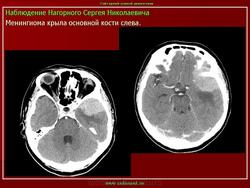

Менингиома

Приложения:

1.meningiomaslayd5.jpg